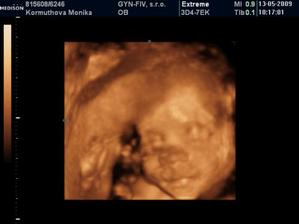

Naše 3D